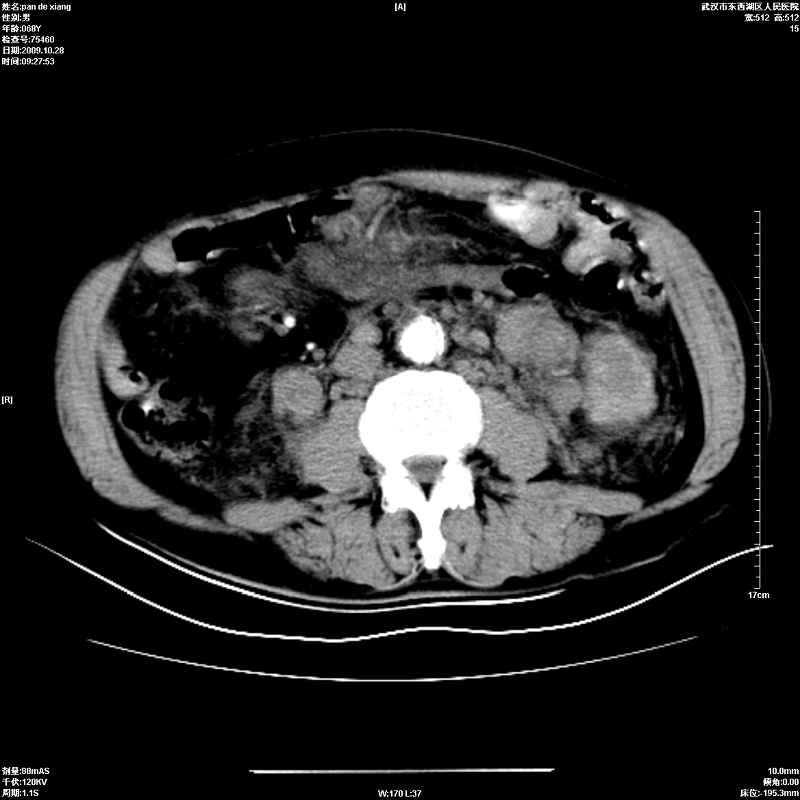

以下是引用杀毒软件在2009-10-28 20:41:00的发言:[br]结合临床考虑---白血病双肾改变或淋巴瘤。

以下是引用zxl51642在2009-10-29 9:59:00的发言:[br]结合临床“单克隆免疫球蛋白血症”,考虑双肾为继发损害并肾功能不全(尿中大量igg及少量iga、igm等大分子免疫球蛋白滤出所致继发损害),椎前软组织肿块为髓外造血。与浆细胞瘤有区别,平扫时有战友说的很清楚。